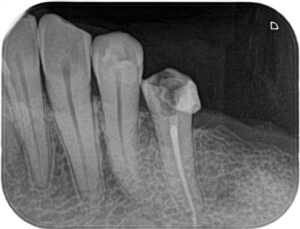

治療前後の比較

Before/After X線写真

痛みの改善と再発防止

治療後、患者さまからは「噛んでも痛みがなくなった」「歯ぐきの腫れが再発しなくなった」と喜びの声をいただきました。